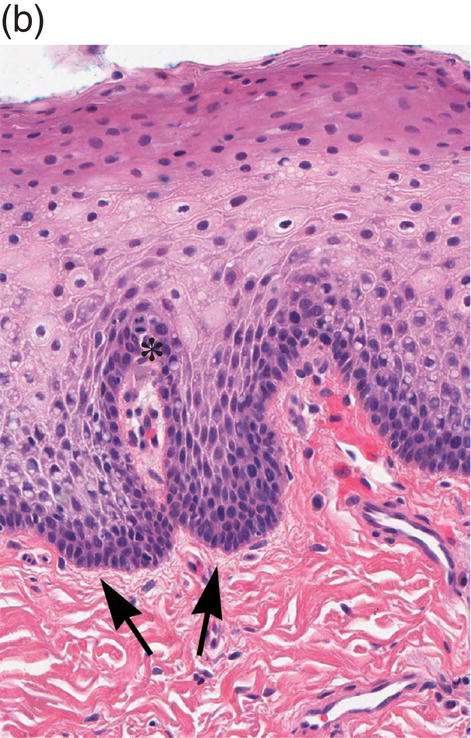

9. What structures are shown by the arrow and what is located in between them?

Explanation

The arrow is indicating the reticular ridges and connective tissue papillae in the skin. Rete ridges are the downward projections of the epidermis into the dermis, while connective tissue papillae are the upward projections of the dermis into the epidermis.